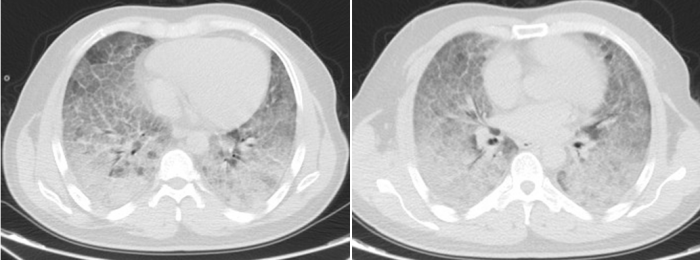

呼吸与危重症医学科三区求诊,当时李贤已出现“大白肺”,在他的胸部CT上几乎看不见正常的肺,血氧饱和度低至40%,随时有心跳呼吸骤停、死亡风险。面对医生转入重症监护室的建议,李贤却因经济压力与心理负担,坚持留在普通病房治疗,不考虑转上级立博体育

李贤胸部CT显示其双肺已呈现“大白肺”状态

历经31天鏖战,李贤的肺部影像从“白茫茫一片”逐渐恢复透亮,鼻导管吸氧下血氧饱和度稳定在90%以上,最终好转出院。患者家属含泪致谢:“是立博体育